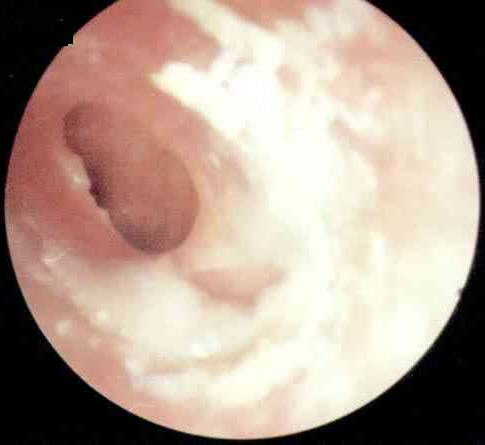

小张前几天患了重感冒,鼻塞、流涕,耳朵还有点闷。自己在家吃了感冒药后鼻子症状好了点,但耳朵症状反而加重了,感到两只耳朵听力下降,打哈欠时耳朵里有水泡声。去西安新城中大耳鼻喉医院耳科诊断为卡他性中耳炎,也称为分泌性中耳炎。

分泌性中耳炎是由于细菌等微生物感染引起的耳部急性炎症,它以鼓室内积液引起听力减退为主要特征。在秋冬季节,它是比较常见的耳部疾病之一。是什么原因引起分泌性中耳炎的呢?耳科的张全安教授指出需从耳部的解剖结构说起。

人们常说人的七窍是相通的。耳朵通过咽鼓管与鼻咽部相通。咽鼓管可以调节耳内的压力,以此与大气压保持平衡,其外还有防御、清洁的功能。在秋冬季,日夜温差比较大,常会诱发上呼吸道感染,炎症波及咽鼓管时,耳内往往会形成负压,这时会产生耳闷的感觉。耳内的黏膜受负压影响分泌较多的液体,并由于咽鼓管功能障碍不能及时排出,积在耳内产生听力下降,耳朵里有水泡声,有时还会感到耳痛。